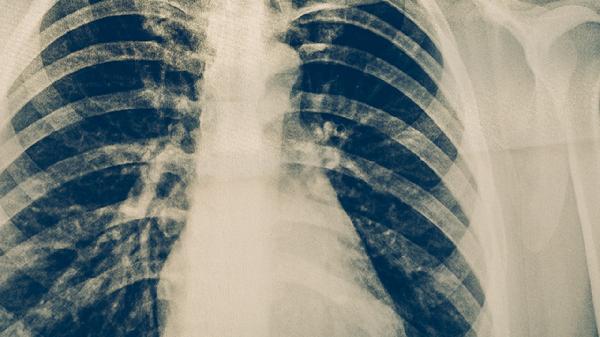

肺癌第一次化疗后身体会有哪些反应

肺癌第一次化疗后可能出现恶心呕吐、骨髓抑制、脱发、疲劳乏力、黏膜炎等反应。化疗药物在杀灭癌细胞的同时也会损伤正常细胞,导致一系列不良反应,多数症状可通过规范处理缓解。